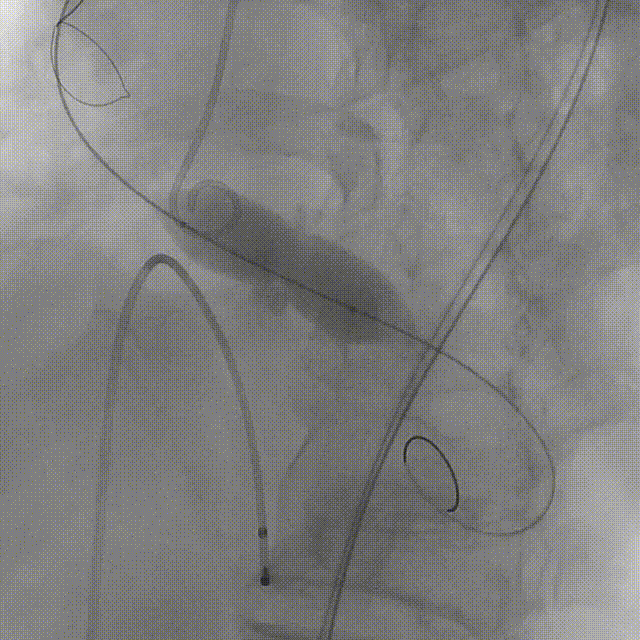

患者病史 主诉:发作性胸闷憋喘半年,加重伴呼吸困难2周。 现病史:患者半年前无明显诱因出现胸闷、憋喘,伴有下肢水肿,2周前上述症状明显加重,夜间不能平卧,痰中带血丝,为进一步诊治再次来我院,门诊以"心力衰竭"收入院。 既往史:肾功能不全、心房颤动 心脏超声提示:LVEF:0.54 1.主动脉瓣病变;2.主动脉瓣狭窄(重度)并反流(中度);3左室壁节段性运动不良;4.升主动脉扩张、双房扩大、左室肥厚;5.二尖瓣硬化并反流(中度);6.三尖瓣反流(轻-中度);7.肺动脉瓣反流;8.肺动脉高压(轻度)PGmean=105mmHg,Vmax=635cm/s,瓣口面积0.27cm²。 术前CT评估 Type0型二叶瓣,重度钙化,钙化集中在瓣叶游离缘,右冠窦为著;左冠高度11.8mm,由于左冠窦部空间较小,左冠风险较高, 升主动脉扩张,最宽处50.5mm;主动脉瓣环水平夹角61.5°,横位心。主动脉弓角77.6°,锐角弓,外周入路在腹主及髂总处有大量散状钙化,胸主处有81.6°的迂曲。 手术策略 推荐右侧股动脉为主入路,左侧股动脉为辅入路,送snare辅助过弯,使用18F大鞘,推荐预装ProStyle A® AV23瓣膜,20mm球囊预扩,初始定位对齐真实瓣环瓣上5mm超高位初始定位释放,释放过程中使瓣膜自然下滑,到工作位观察瓣膜形态,最终理想位置0-瓣下3mm。 手术过程 Step1:右侧股动脉为主入路、左侧股动脉为辅入路,成功穿刺并送入 18F 大鞘; Step2:主动脉根部造影,瓣口限制重 Step3:Type 0 型二叶瓣畸形合并重度钙化,患者瓣口狭窄严重,同时横位心,不仅导丝跨瓣困难,导管更难进入;术者凭借精湛操作,将导丝顺利跨瓣,反复微调导管角度,最终导管顺利过瓣。 导丝精准跨瓣 Step4:20mm球囊跨瓣困难,snare辅助下球囊成功跨瓣,预扩有腰无漏,冠脉充盈良好。 Step5: snare辅助下成功跨瓣,可以看到系统过弓形态瓣膜仓柔软,过弓顺滑 输送系统过弓 Step6:初始定位瓣上5mm开始释放,释放部分后观察瓣架下缘内收明显,后回收系统重新定位 初始定位 底部内收 Step7:瓣膜完全释放前,血压一度降低,术者迅速调整器械,实现瓣膜迅速锚定,快速释放 完全释放 Step8:20mm球囊后扩 最终造影,位置(瓣下3mm)形态良好 手术难点 患者不仅有主动脉瓣重度狭窄,还叠加肾功能不全、心房颤动等基础疾病,术中血流动力学波动极易引发心功能衰竭。ProStyle A® 预装干瓣“开包即用” 的特性压缩了术者操作时间,80%可回收设计给了术者容错空间,而这些看似难以逾越的难关,最终被团队精湛的医术一一化解,术中对于导丝、导管、球囊等器械每一步的精准操控,再到突发状况的从容处置,无不彰显着团队深厚的专业积淀与顶尖的操作技艺。 结语 此次手术的圆满成功,不仅彰显了陈玉国、李传保教授团队在复杂结构性心脏病介入治疗领域深厚的专业造诣与攻坚克难的决心,也充分验证了ProStyle A®系统在应对复杂高难度病例时的卓越适用性与有效性。 作为扎根齐鲁、享誉全国的医疗高地,山东大学齐鲁医院始终赓续着这片热土的仁厚文脉,将“医道从德,术业求精”的院训精神镌刻在每一次诊疗实践之中。特别是在结构性心脏病诊疗领域,医院团队始终怀揣医者担当,勇攀医学高峰,不断以更前沿的技术突破,为危重患者点亮重获新生的希望。 专家简介 陈玉国 山东大学齐鲁医院(点击查看专家详细简历) 李传保 山东大学齐鲁医院(点击查看专家详细简历) · END ·

最终造影